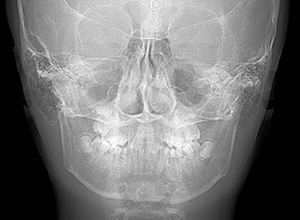

X-Ray

X-Ray所見

セファロ所見 下顎骨は比較的バランスが良いもののセラに対して下顎等は後方に位置しており中顔面部の奥行きもあることから顔面高さは低くなっていた。

パノラマ所見 上下顎第三大臼歯は埋伏歯しており、上顎右側犬歯は先天欠如をしていた。